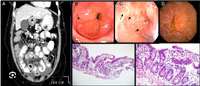

CẬP NHẬT VỀ HÌNH ẢNH MÔ BỆNH HỌC VIÊM HỆ TIÊU HÓA TĂNG BCAT

Đại thể

·Hình ảnh không đặc hiệu trên bề mặt niêm mạc, gồm niêm mạc dày lên, sung huyết đỏ, loét xói khuyết và loét tiêu hóa, hình thành các mảng trắng, phù nề, giãn các mạch máu hoặc hình thành nốt dưới niêm mạc.

Vi thể

·Chẩn đán đòi hỏi xác định bằng phân tích mô bệnh học dạ dày, ruột non, ruột già hoặc sinh thiết (Adv Anat Pathol 2011;18:335) !important;